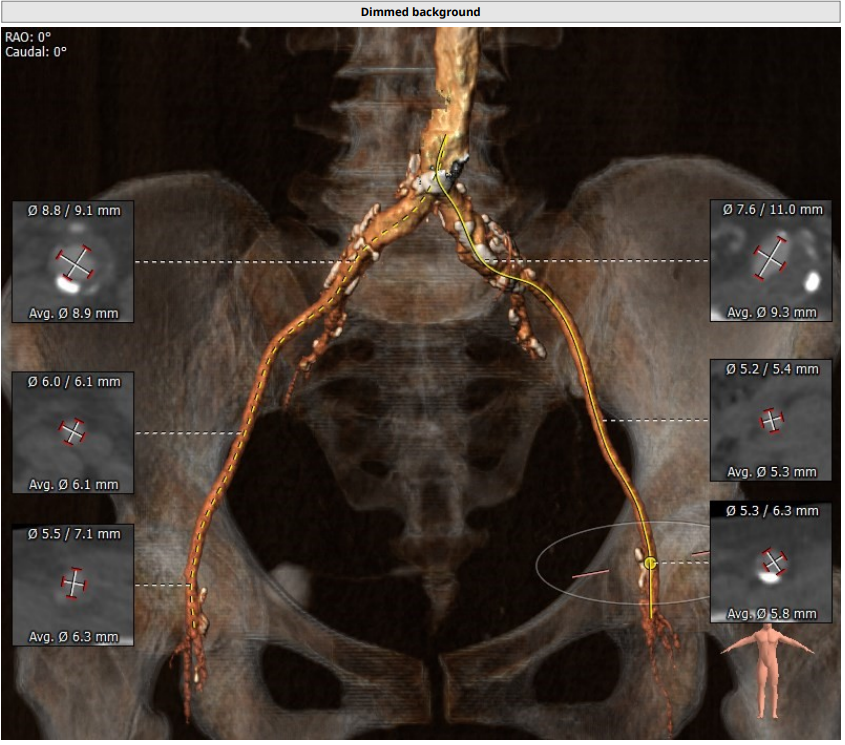

术前CT分析:

· 三叶瓣,中度钙化。整体结构呈上小下大,法式窦结构小,左冠瓣叶长度较长,流出道大。

· 冠脉严重钙化、提示严重冠心病。

· 难点:选择大号瓣膜担心冠脉风险,选择小号瓣膜担心瓣周漏。

· 29%的术前EF值,球扩后循环崩溃的风险极高。

瓣环平均直径:24.0mm,左室流出道平均直径:25.2mm

左冠窦:25.5mm,右冠窦:22.6mm,无冠窦:28.7mm,

窦管交界处:22.9mm

升主未见明显增宽:34mm,心脏角度:41°

钙化积分:501mm³,中重度钙化

左冠高度:10.9mm,右冠高度12.7mm

心室明显增大

双侧股动脉-髂动脉钙化,髂外动脉